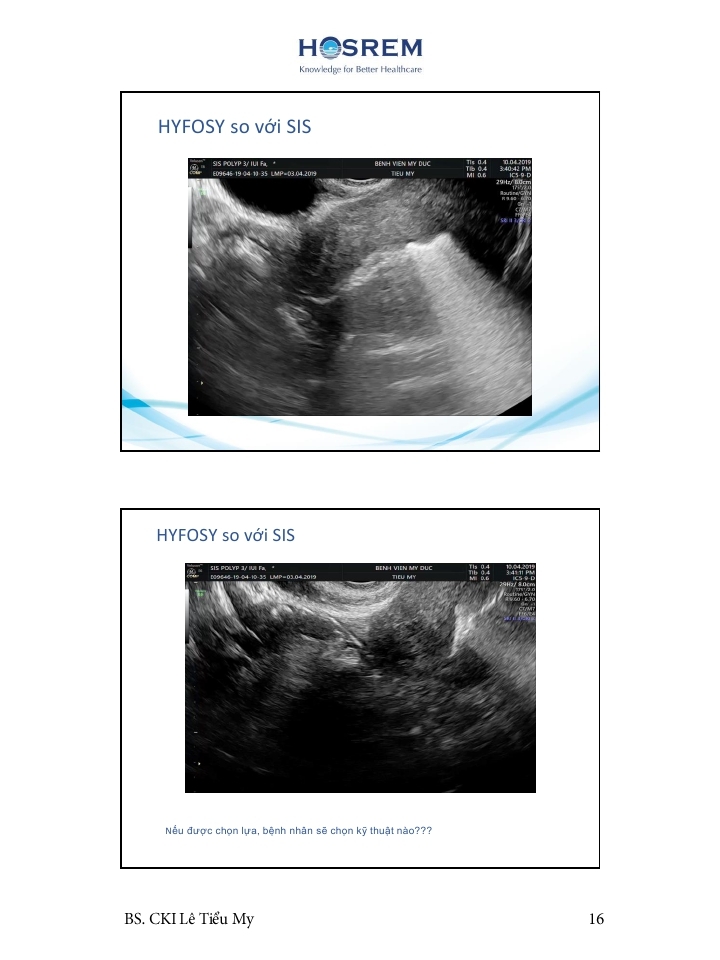

Các phương pháp đánh giá ống dẫn trứng